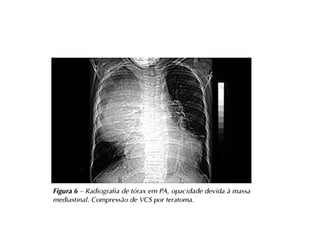

Tórax e Coração

● Dispneia e palpitação

● ICC descompensada

● Angina Pectoris

● Tosse

● Dor Torácica (esterno, herpes zoster, fraturas…)

● Sopro Sistólico